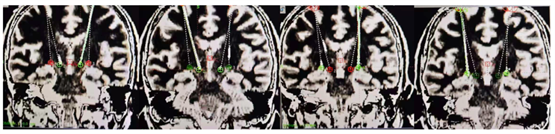

手术的成功离不开精准的术前规划和精细的术中操作。团队通过术前MRI与CT影像融合技术,结合专业手术计划系统,精准确定手术靶点和复杂路径。最终,仅通过两个直径14mm的骨孔,就成功完成了双侧4根刺激电极的精准植入,同时覆盖双侧STN/GPi靶点。术后重建影像显示,4根电极均“十环”命中目标靶点,手术过程十分顺利。

双骨孔精准植入四根电极